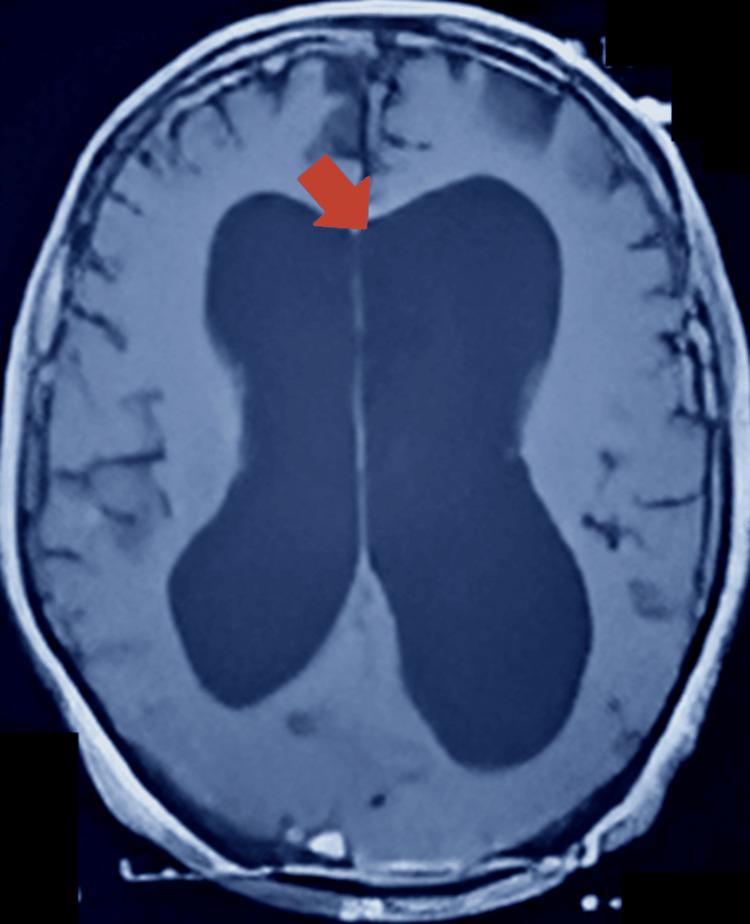

Dandy-Walker malformation is the most prevalent posterior fossa anomaly. Dandy-Walker variant, or Dandy-Walker complex, are terms devised to contrast those conditions that do not meet the standard of Dandy-Walker malformation. Dandy-Walker malformation is usually a congenital diagnosis. Our case calls attention to an extraordinary presentation of Dandy-Walker malformation in adulthood. A 76-year-old male patient initially presented to the Emergency Department at Dow University Hospital at Ojha Campus on the grounds of suspicion of a respiratory infection. COVID-19 was suspected; however, polymerase chain reaction (PCR) testing yielded a negative result. The patient later developed an erythematous and swollen left arm, which pointed towards a diagnosis of cellulitis, and the patient was managed accordingly. After being moved to the General Medicine Ward, our team noted that the patient was bed-bound and conducted a neurological exam, in which he presented with incoordination, less brisk and pendular deep tendon reflexes, and hypotonia in lower limbs, all suggestive of cerebellar involvement. The patient was also lethargic and was in a state of confusion, suggesting an altered mental status. Subsequent labs were completed, and bacterial pneumonia was confirmed on pleural fluid analysis. A CT scan of the head and an MRI scan of the brain were also ordered to investigate the reason for neurological involvement. The imaging displayed hallmarks signifying Dandy-Walker malformation, such as enlargement of the fourth ventricle, hypoplastic vermis, and posterior fossa anomalies.

丹迪-沃克畸形是最常见的后颅窝异常。丹迪-沃克变异型或丹迪-沃克复合体是为了与那些不符合丹迪-沃克畸形标准的情况相区分而设计的术语。丹迪-沃克畸形通常是一种先天性诊断。我们的病例提醒人们注意丹迪-沃克畸形在成年期的一种特殊表现。一名76岁男性患者最初因疑似呼吸道感染被送往奥贾校区的道大学医院急诊科。怀疑感染了新冠病毒;然而,聚合酶链反应(PCR)检测结果为阴性。患者后来左臂出现红斑和肿胀,这表明诊断为蜂窝织炎,并对患者进行了相应治疗。转至普通内科病房后,我们的团队注意到患者卧床不起,并进行了神经系统检查,检查发现他存在共济失调、深部腱反射减弱且呈摆动样、下肢肌张力减退,所有这些都提示小脑受累。患者还嗜睡且处于意识模糊状态,提示精神状态改变。随后完成了各项实验室检查,胸腔积液分析确诊为细菌性肺炎。还安排了头部CT扫描和脑部MRI扫描以调查神经系统受累的原因。影像学检查显示出表明丹迪-沃克畸形的特征,如第四脑室扩大、小脑蚓部发育不全和后颅窝异常。